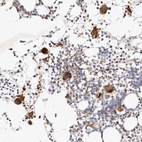

Immunohistochemical staining of human bone marrow shows strong cytoplasmic positivity in megakaryocytes.